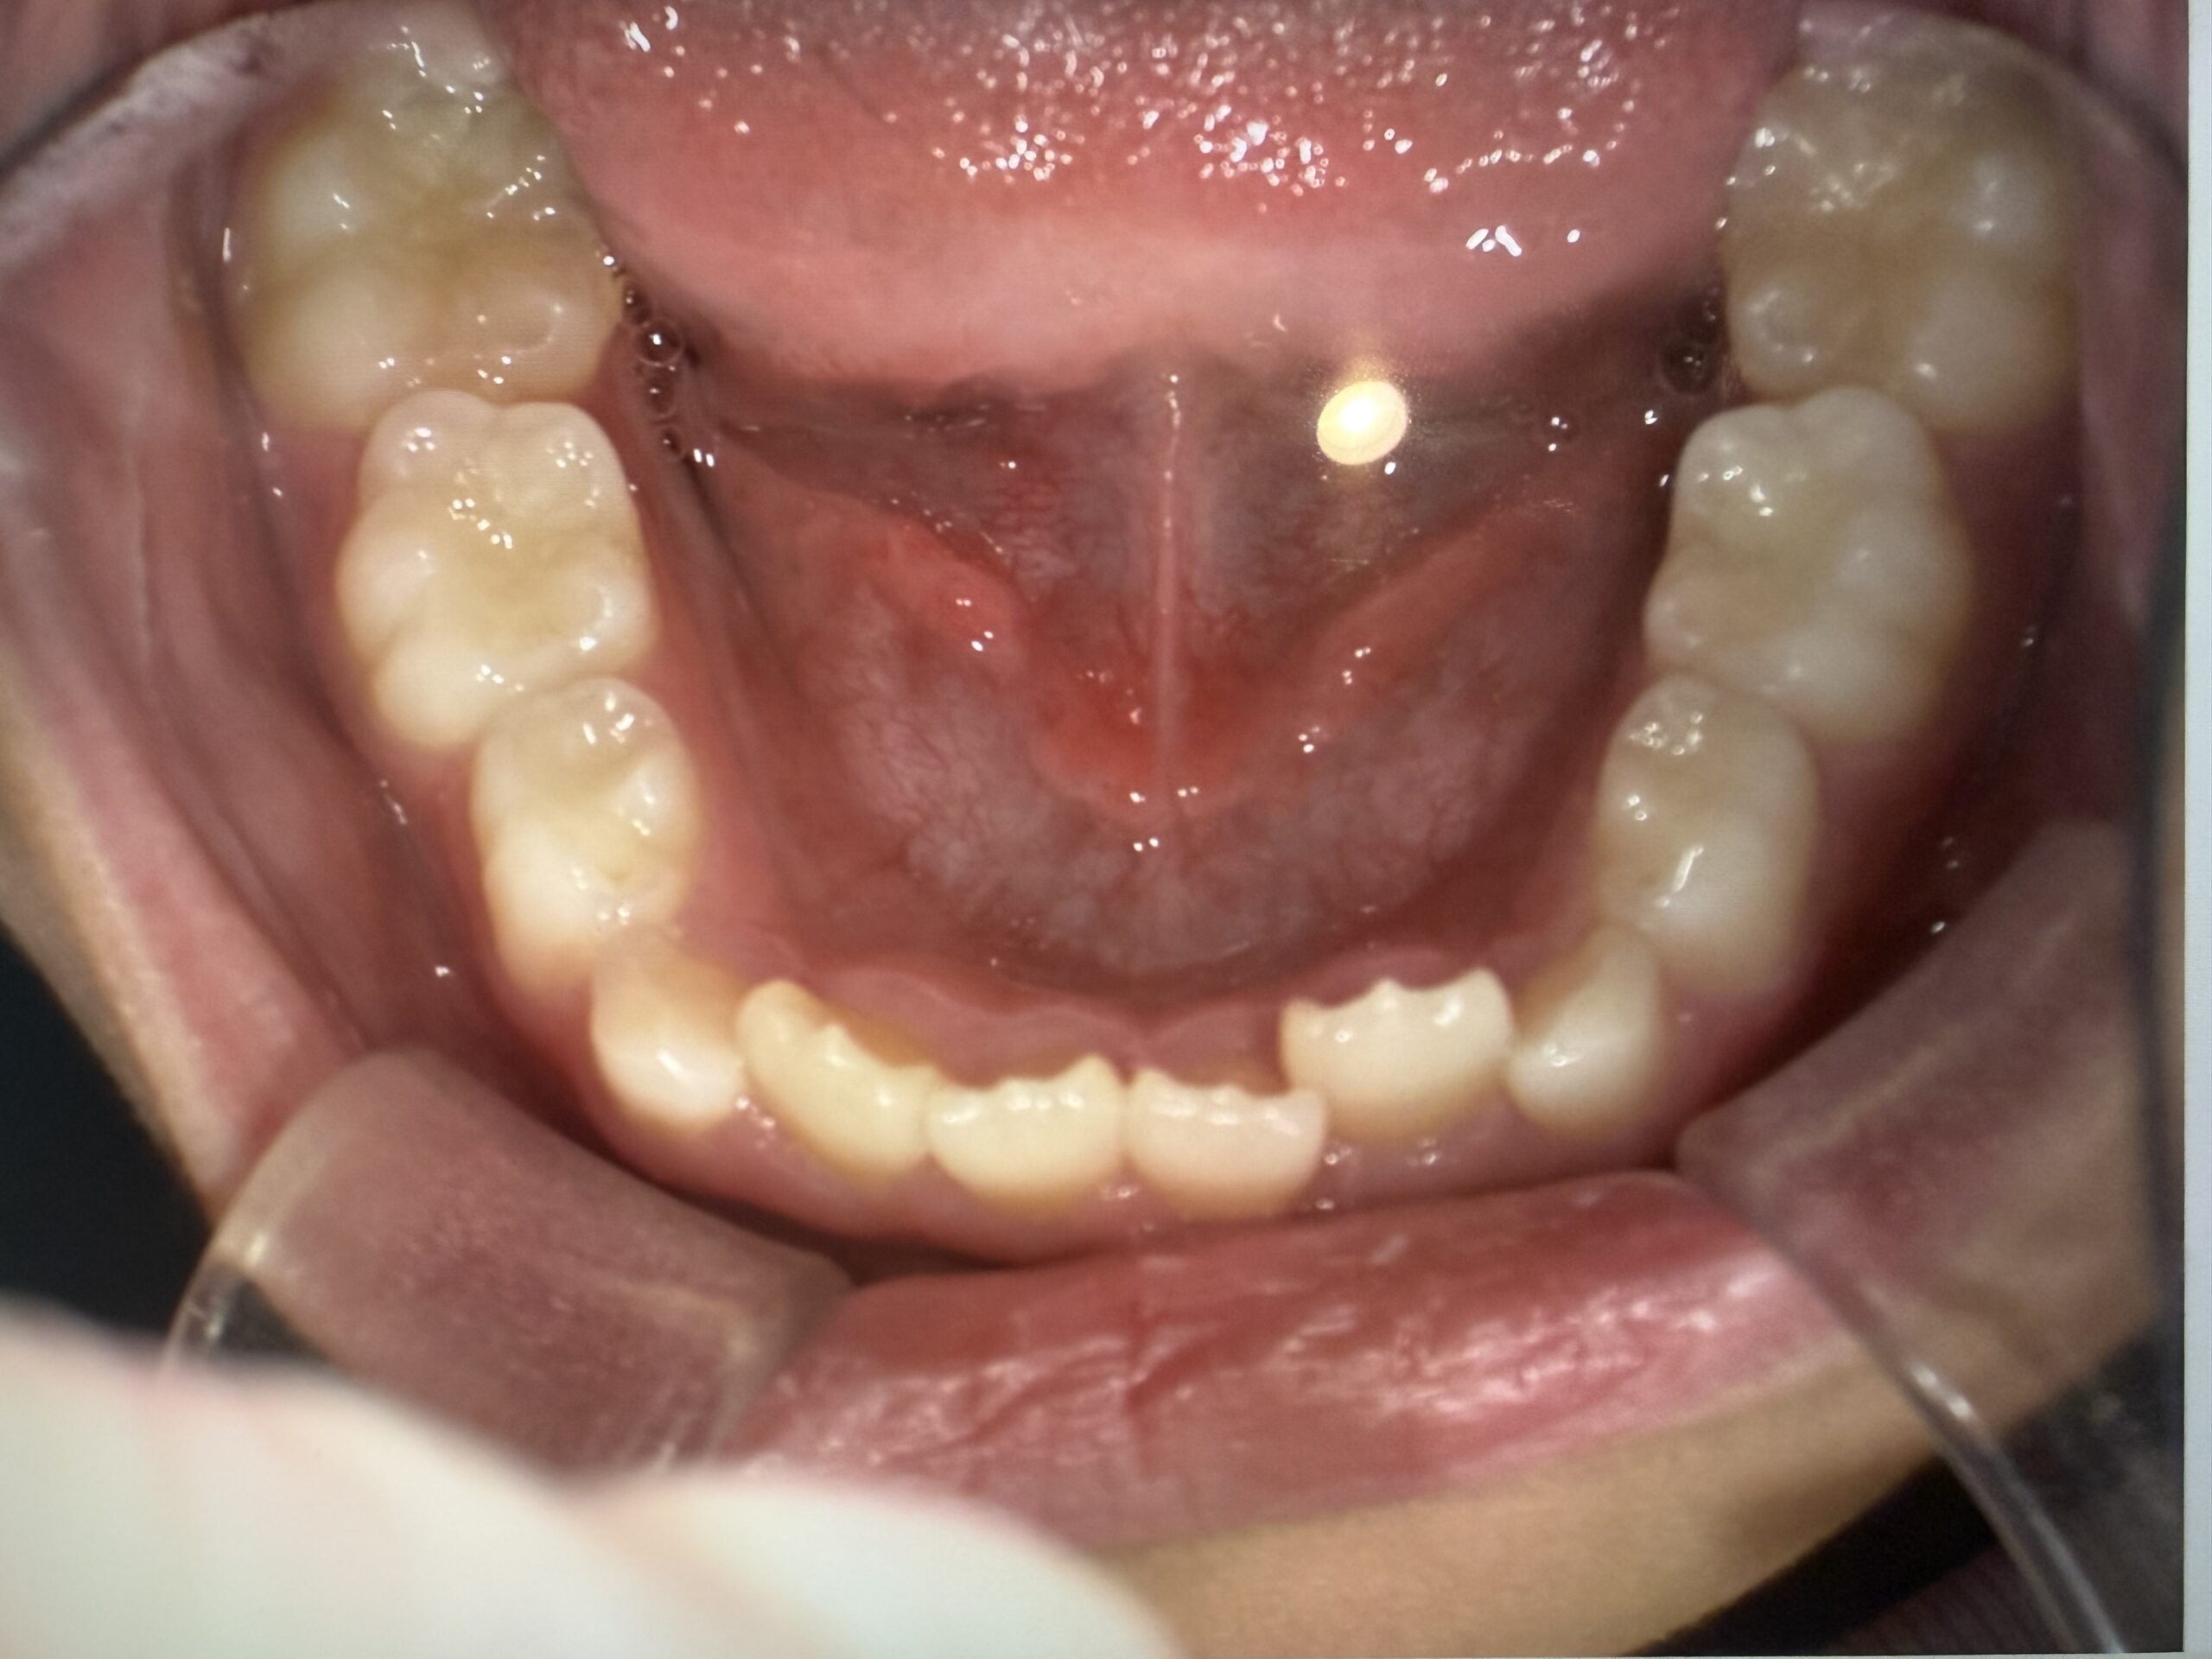

虫歯治療decay

歯周病perio

予防歯科preventive